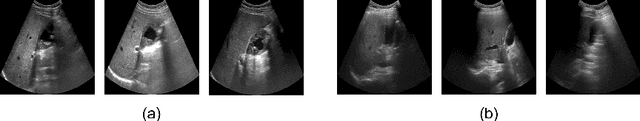

Abstract:In recent years, automated Gallbladder Cancer (GBC) detection has gained the attention of researchers. Current state-of-the-art (SOTA) methodologies relying on ultrasound sonography (US) images exhibit limited generalization, emphasizing the need for transformative approaches. We observe that individual US frames may lack sufficient information to capture disease manifestation. This study advocates for a paradigm shift towards video-based GBC detection, leveraging the inherent advantages of spatiotemporal representations. Employing the Masked Autoencoder (MAE) for representation learning, we address shortcomings in conventional image-based methods. We propose a novel design called FocusMAE to systematically bias the selection of masking tokens from high-information regions, fostering a more refined representation of malignancy. Additionally, we contribute the most extensive US video dataset for GBC detection. We also note that, this is the first study on US video-based GBC detection. We validate the proposed methods on the curated dataset, and report a new state-of-the-art (SOTA) accuracy of 96.4% for the GBC detection problem, against an accuracy of 84% by current Image-based SOTA - GBCNet, and RadFormer, and 94.7% by Video-based SOTA - AdaMAE. We further demonstrate the generality of the proposed FocusMAE on a public CT-based Covid detection dataset, reporting an improvement in accuracy by 3.3% over current baselines. The source code and pretrained models are available at: https://gbc-iitd.github.io/focusmae